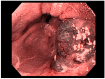

Gastric and esophageal tumors are diverse neoplasms that involve mucosal and submucosal tissue layers and include squamous cell carcinomas, adenocarcinomas, spindle cell neoplasms, neuroendocrine tumors, marginal B cell lymphomas, along with less common tumors. The worldwide burden of esophageal and gastric malignancies is significant, with esophageal and gastric cancer representing the ninth and fifth most common cancers, respectively. The approach to diagnosis and staging of these lesions is multimodal and includes a combination of gastrointestinal endoscopy, endoscopic ultrasound, and cross-sectional imaging. Likewise, therapy is multidisciplinary and combines therapeutic endoscopy, surgery, radiotherapy, and systemic chemotherapeutic tools. Future directions for diagnosis of esophageal and gastric malignancies are evolving rapidly and will involve advances in endoscopic and endosonographic techniques including tethered capsules, optical coherence tomography, along with targeted cytologic and serological analyses.